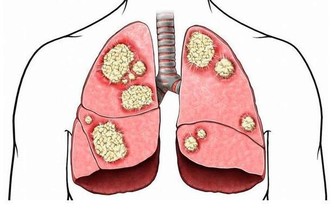

醫學研究證明,在控制喝酒的情況下,如果每天食用奶製品,包括牛奶及酸奶等,患上肝癌的機率將減少78%。目前小孩已經養成了食用奶製品的習慣,但成年人中食用奶製品的還為數不多,不妨加以改進。

喝茶,對防肝癌很有益,尤其是喝一些護肝茶。比如:玉蘭根茶

玉蘭根,藥用價值很高,有很好的保肝作用,其可其加速磷脂合成的膽鹼存在,因而可加速細胞修復速度,對肝臟細胞有明顯的保護作用。玉蘭根根提取物中脂溶性成分和水溶性成分對化學性或酒精性肝損傷均具有顯著的保護作用。

所以,選擇用玉蘭根泡水喝,或者製成玉蘭根茶,可加速肝細胞修復,護肝保肝效果很好。

發霉食品中的黃曲霉毒素為致肝癌物質,致癌所需時間最短僅為24週,